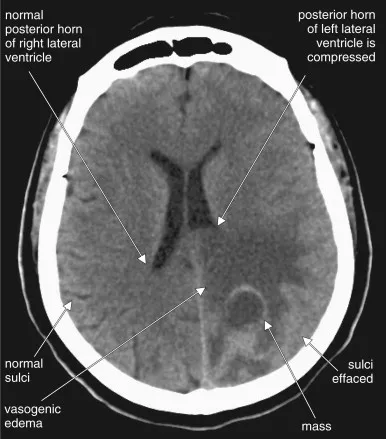

- Imaging (CT/MRI): Sulcal effacement, ventricular compression.